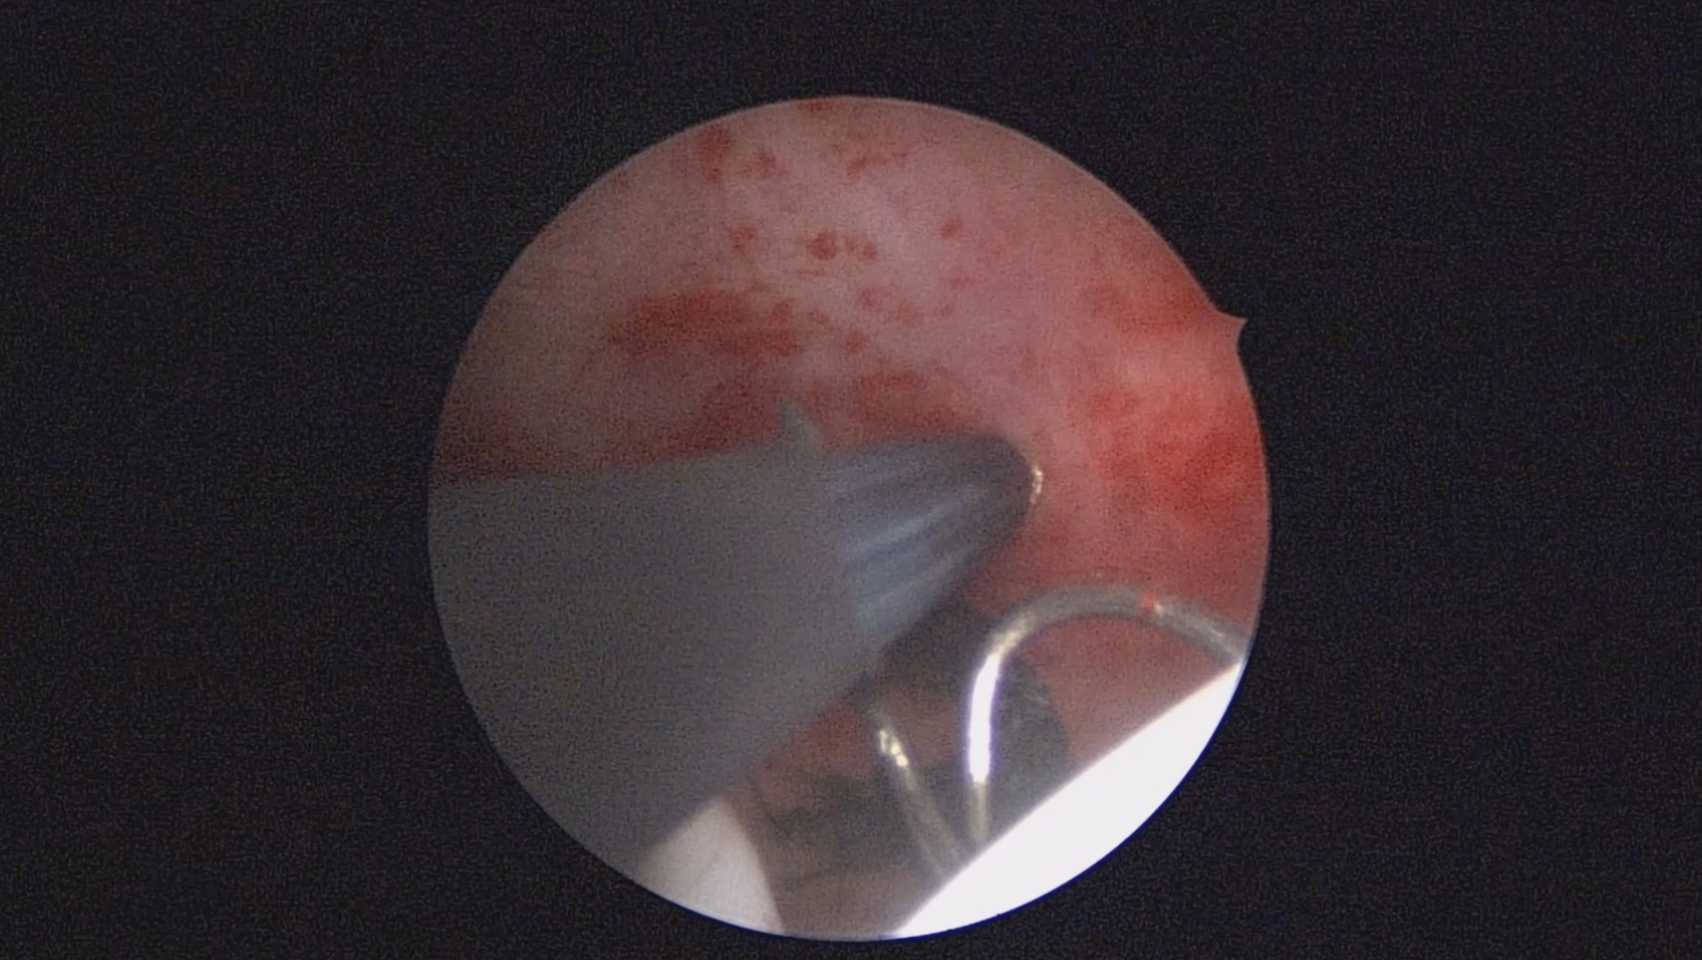

患者40岁,G0P0,原发不孕10+年,20+岁严重痛经,多家医院行腹腔镜手术治疗腺肌症合并多发性肌瘤,宫腔镜切除内膜息肉,前后肌注GnRH-a6针,痛经明显缓解。2017年试管助孕一次,失败,放弃生育需求,现要求放置曼月乐环并固定。2024年5月行宫腔镜下曼月乐不锈钢挂钩固定,子宫前位,宫深7cm,宫腔形态正常,宫内膜正常,双侧输卵管开口可见,将曼月乐环用4号丝线与挂钩连接并固定于宫底(第一次做宫腔镜下节育环固定,没有想到利用曼月乐尾丝连接环)。2024年6月复查B超,曼月乐固定装置扎入宫底肌层0.46cm,环位置正常,2025年5月复查B超,曼月乐顶端距宫底1.5cm。